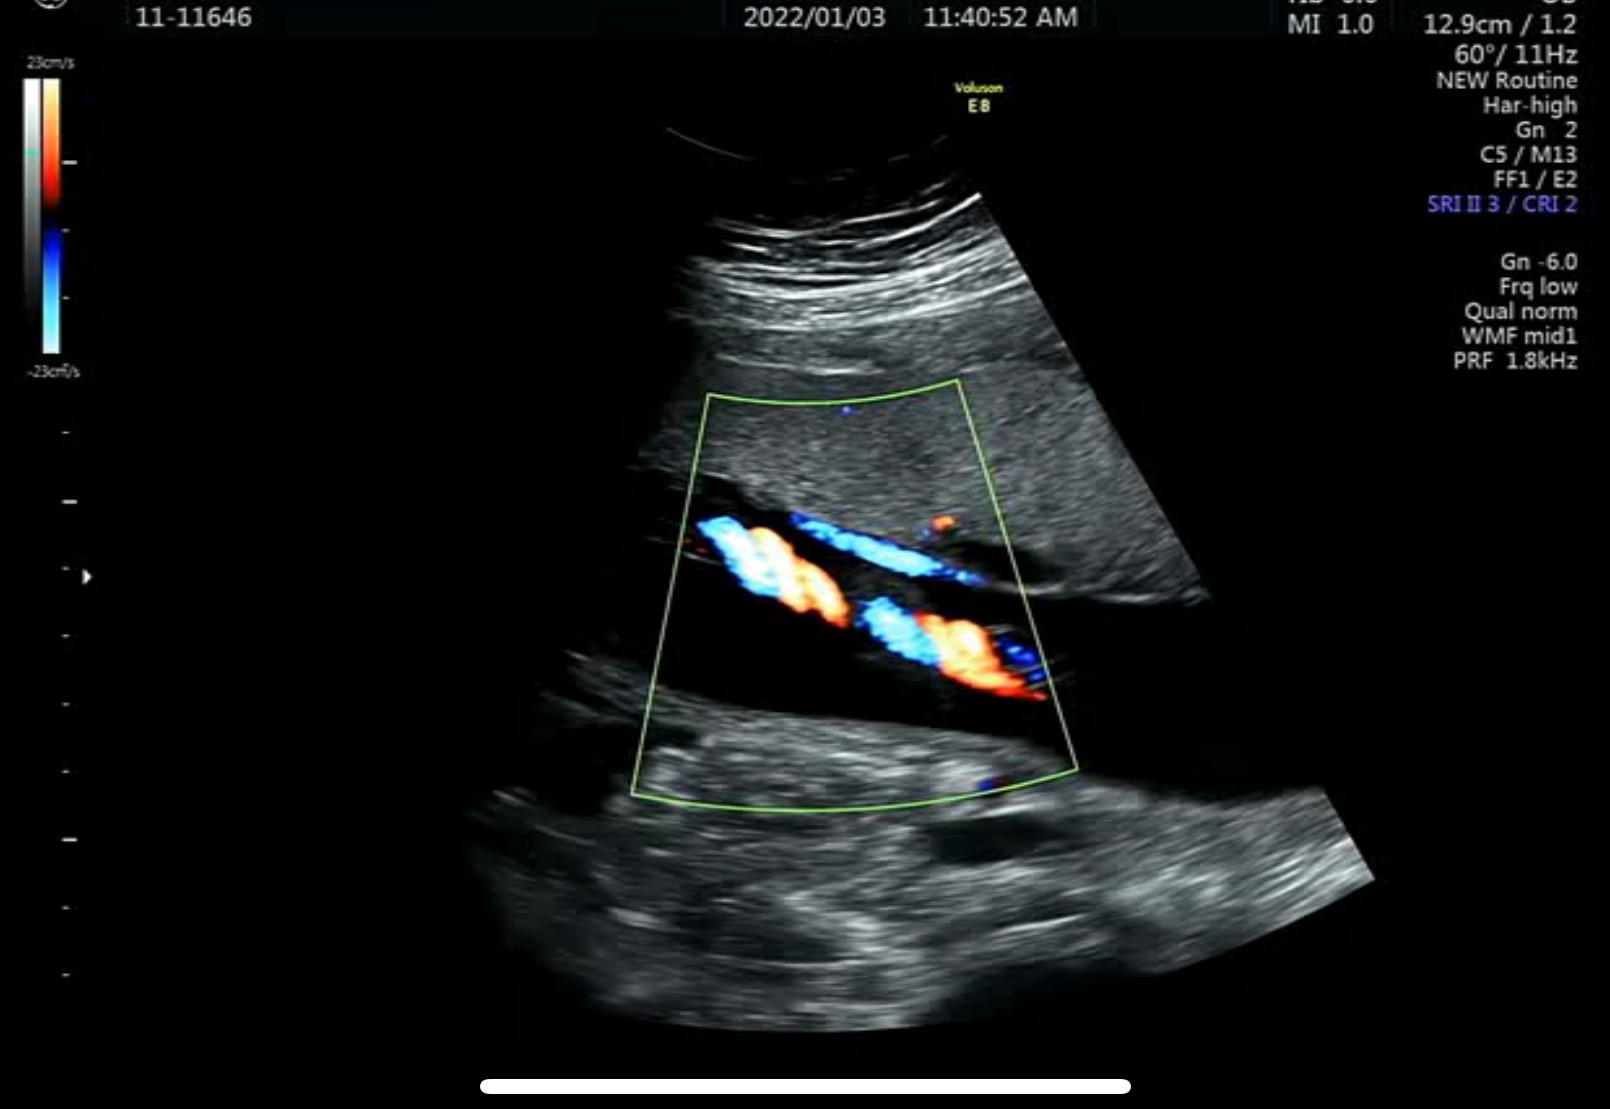

심장으로 들락날락하는 혈관도 괜찮다고 하고